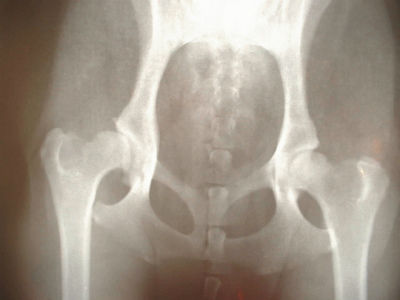

Q:骨粗鬆症予防というほどではありませんが、以前、体組成計で計った際に骨密度が平均よりも低かったので、カルシウム剤やカルシウムサプリを利用してきました。ところが、先日の再測定では、更に骨密度が低下していました。一体全体、どうしたら良いか解りません。牛乳も頑張って飲んでいるのですが・・・。さて、これまでに骨密度が低下する理由として、カルシウム不足由来ではないケースが多数あることを紹介してきました。

ミネラル摂取量とタイミング、組み合わせに関しては、非常に頭を巡らせる必要があるのです。カルシウムサプリもまた鉄サプリ同様、安易に高単位の物を自己流で摂取すべきではありません。